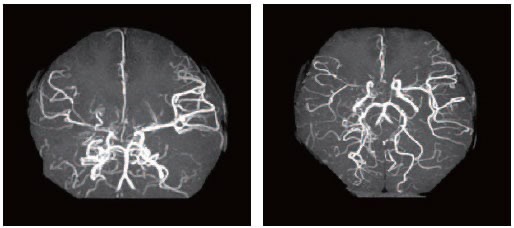

모야모야병은 뇌혈관, 특히 뇌로 혈액을 공급하는 내경동맥과 그 주변 주요 혈관이 점점 좁아지고 막히는 희귀 난치성 질환으로, 혈류가 줄어든 뇌는 부족한 혈액을 보충하기 위해 가느다란 미세측부혈관들을 새로 만들어냅니다. 이 작은 혈관들이 연기처럼 보인다고 하여 일본어로 ‘모야모야(안개·연기)’라는 이름이 붙었습니다. 소아부터 성인까지 폭넓게 나타나며, 특히 5~10세 어린이와 30대 전후의 여성에서 비교적 많이 발견되는 경향이 있습니다. 증상은 일시적 마비, 언어장애, 두통, 실신, 경련 등 매우 다양해 뇌졸중과 유사하거나 초기에는 가벼운 신경학적 증상으로만 나타나 진단이 늦어지기도 했습니다. 질환이 진행하면 허혈성 뇌졸중(뇌경색)이나 출혈성 뇌졸중 위험이 증가하여 반드시 전문적인 관리가 필요합니다. 아직 완전히 예방할 수 있는 방법은 없지만 조기 진단과 적절한 치료를 통해 뇌 기능을 보호하고 삶의 질을 유지할 수 있습니다.

모야모야병은 뇌기저부의 주요 혈관이 서서히 협착되고 막히면서 뇌혈류가 감소하는 만성 진행성 뇌혈관 질환입니다. 협착이 진행된 부위를 대신해 뇌는 생존을 위해 얇고 약한 혈관망을 만들어 혈류를 보충하려 하고, 이 새로운 혈관들이 촬영 영상에서 연기처럼 퍼져 보인다고 하여 ‘모야모야’라는 이름이 붙었습니다. 기전적으로는 내경동맥 말단부와 중대뇌동맥·전대뇌동맥의 기시부에 병변이 가장 잘 생기며, 시간이 지남에 따라 양쪽에 대칭적으로 나타나는 특징을 보였습니다. 이 질환은 단순한 혈관 협착이 아니라 진행성 변화이기 때문에 치료하지 않으면 혈류 부족이 심해지고 뇌 손상이 누적될 수 있습니다. 또한 뇌기능이 체력·호흡·체온 변화 등에 민감하게 반응하기 때문에 과호흡, 울음, 격렬한 운동, 감염 등으로 증상이 악화될 수 있습니다. 즉, 모야모야병은 시간이 지나면서 뇌혈류를 감소시키고 뇌졸중 위험을 높이는 질환이며, 평생 관리가 필요한 만성적 특성을 갖고 있습니다.

따라서 가족력이 있거나 의심되는 증상이 있다면 뇌 MRA·MRI 등의 정기검진이 도움이 되며, 조기 진단 시 치료 효과도 훨씬 높아집니다.